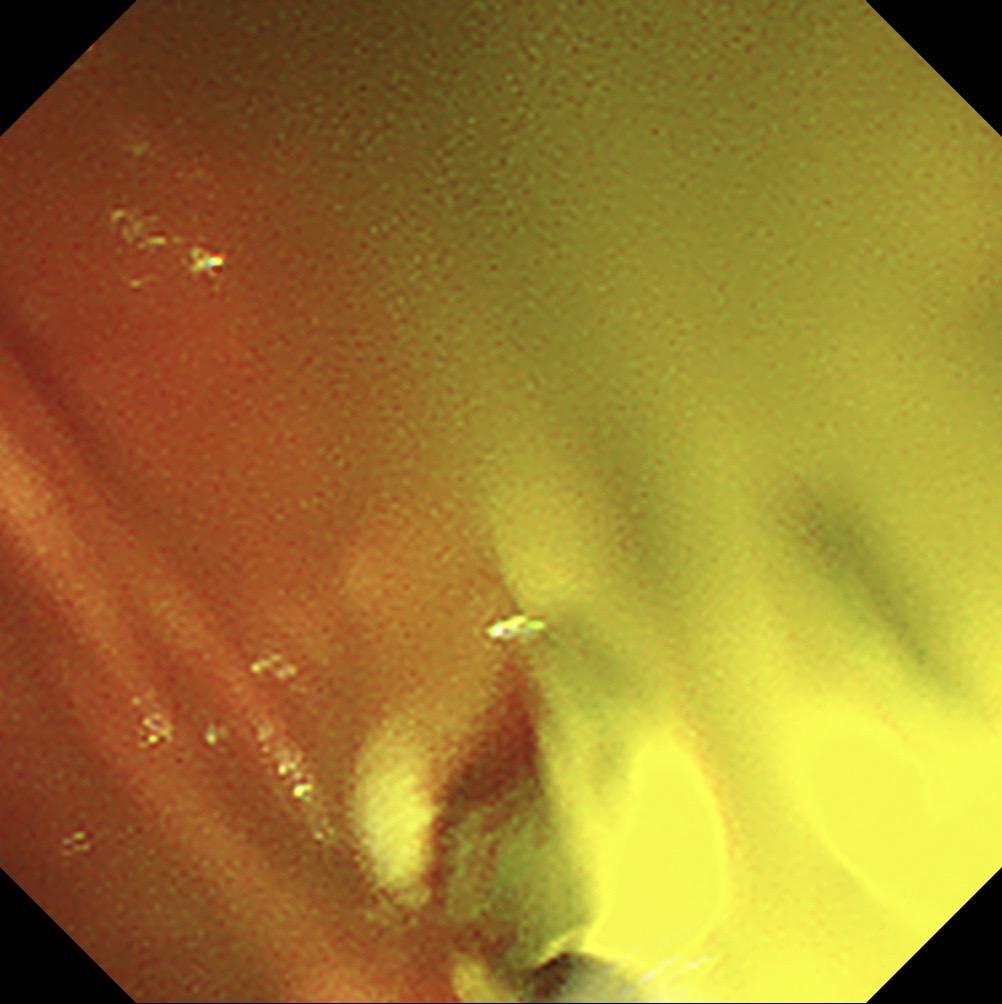

周末胆管结石化脓性胆管炎急诊ERCP.患者胆囊切除术后,这次因胆管结石腹痛来住院,患者一直服用阿司匹林没法直接手术,想让患者停够七天后再手术。住院第三天患者腹痛持续不缓解,黄疸升到快两百,没办法只能周末急诊手术,先放塑料支架解除患者的痛苦,下一次再取结石!患者家庭条件一般,想尽量帮患者省点花费,结果还是没办法……